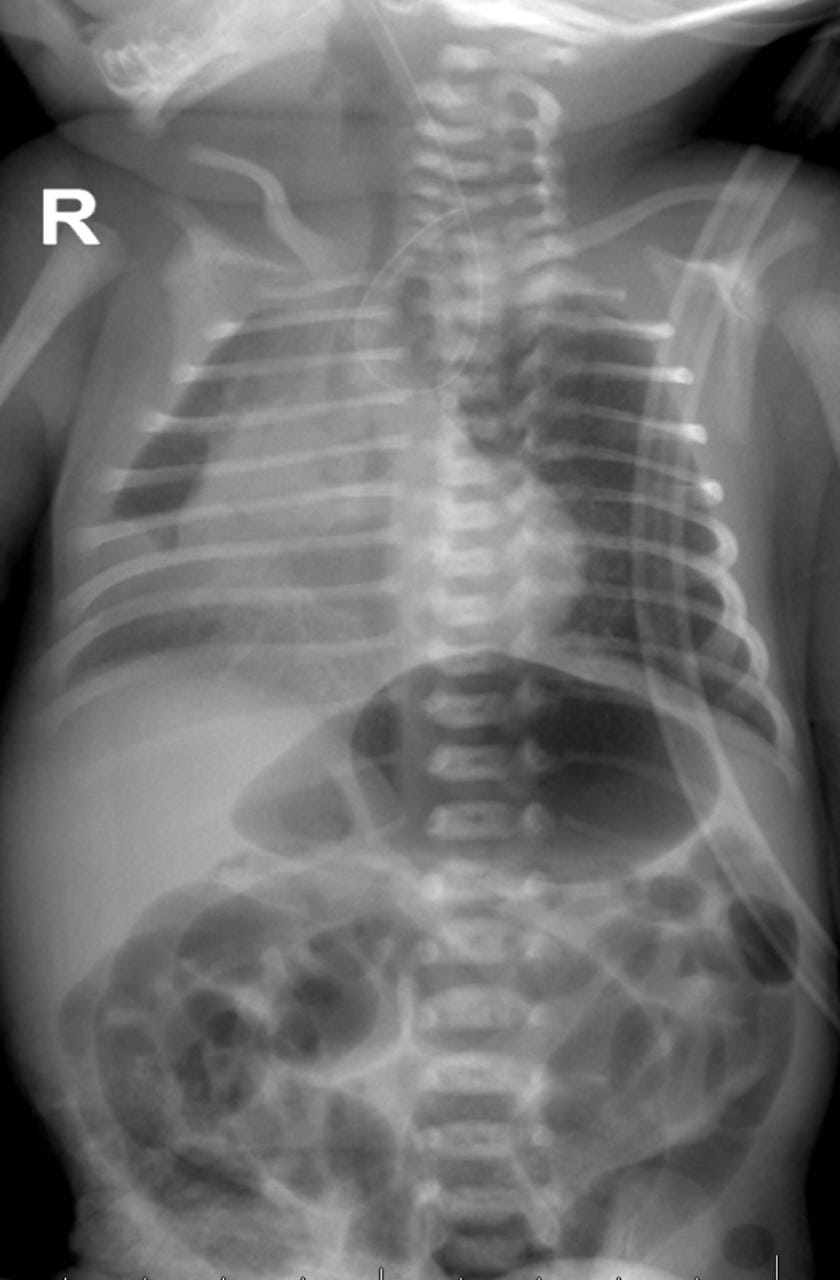

أجرى فريق طبي من أطباء جراحة أطفال واستشاريين التخدير وفنيين العمليات، عملية جراحية لمدة 3 ساعات، وذلك لتصحيح عيب خلقي في طفل حديث الولادة خديج بعمر خمسة أيام.

وأنجز الفريق الطبي رتق المريء مع ناسور رغامي مريئي تكللت بالنجاح والمريض بحالة جيدة، ويتلقى بقية الخطة العلاجية.